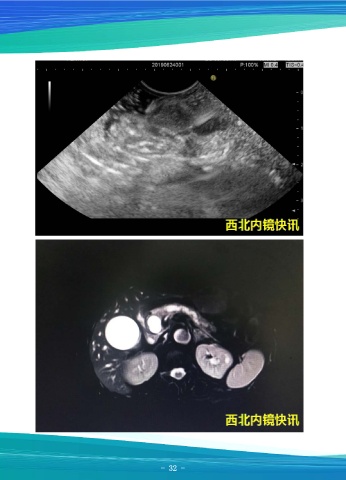

一例胆囊泥沙样结石并胆总管壁炎性增厚

资料提供:马师洋 西安交大二附院消化内科

患者女,42岁,超声内镜示:见胰腺回声增高,头部直径33mm,体部直径16mm,

尾部直径26mm,胰管未见扩张,最宽2.7mm,管壁高回声,胰腺体尾部实质内见高

回声点及高回声条带,未见胰管内结石,胆总管壁回声稍增厚,乳头未见异常,降段见

憩室,胆囊内见胆泥及结石回声。